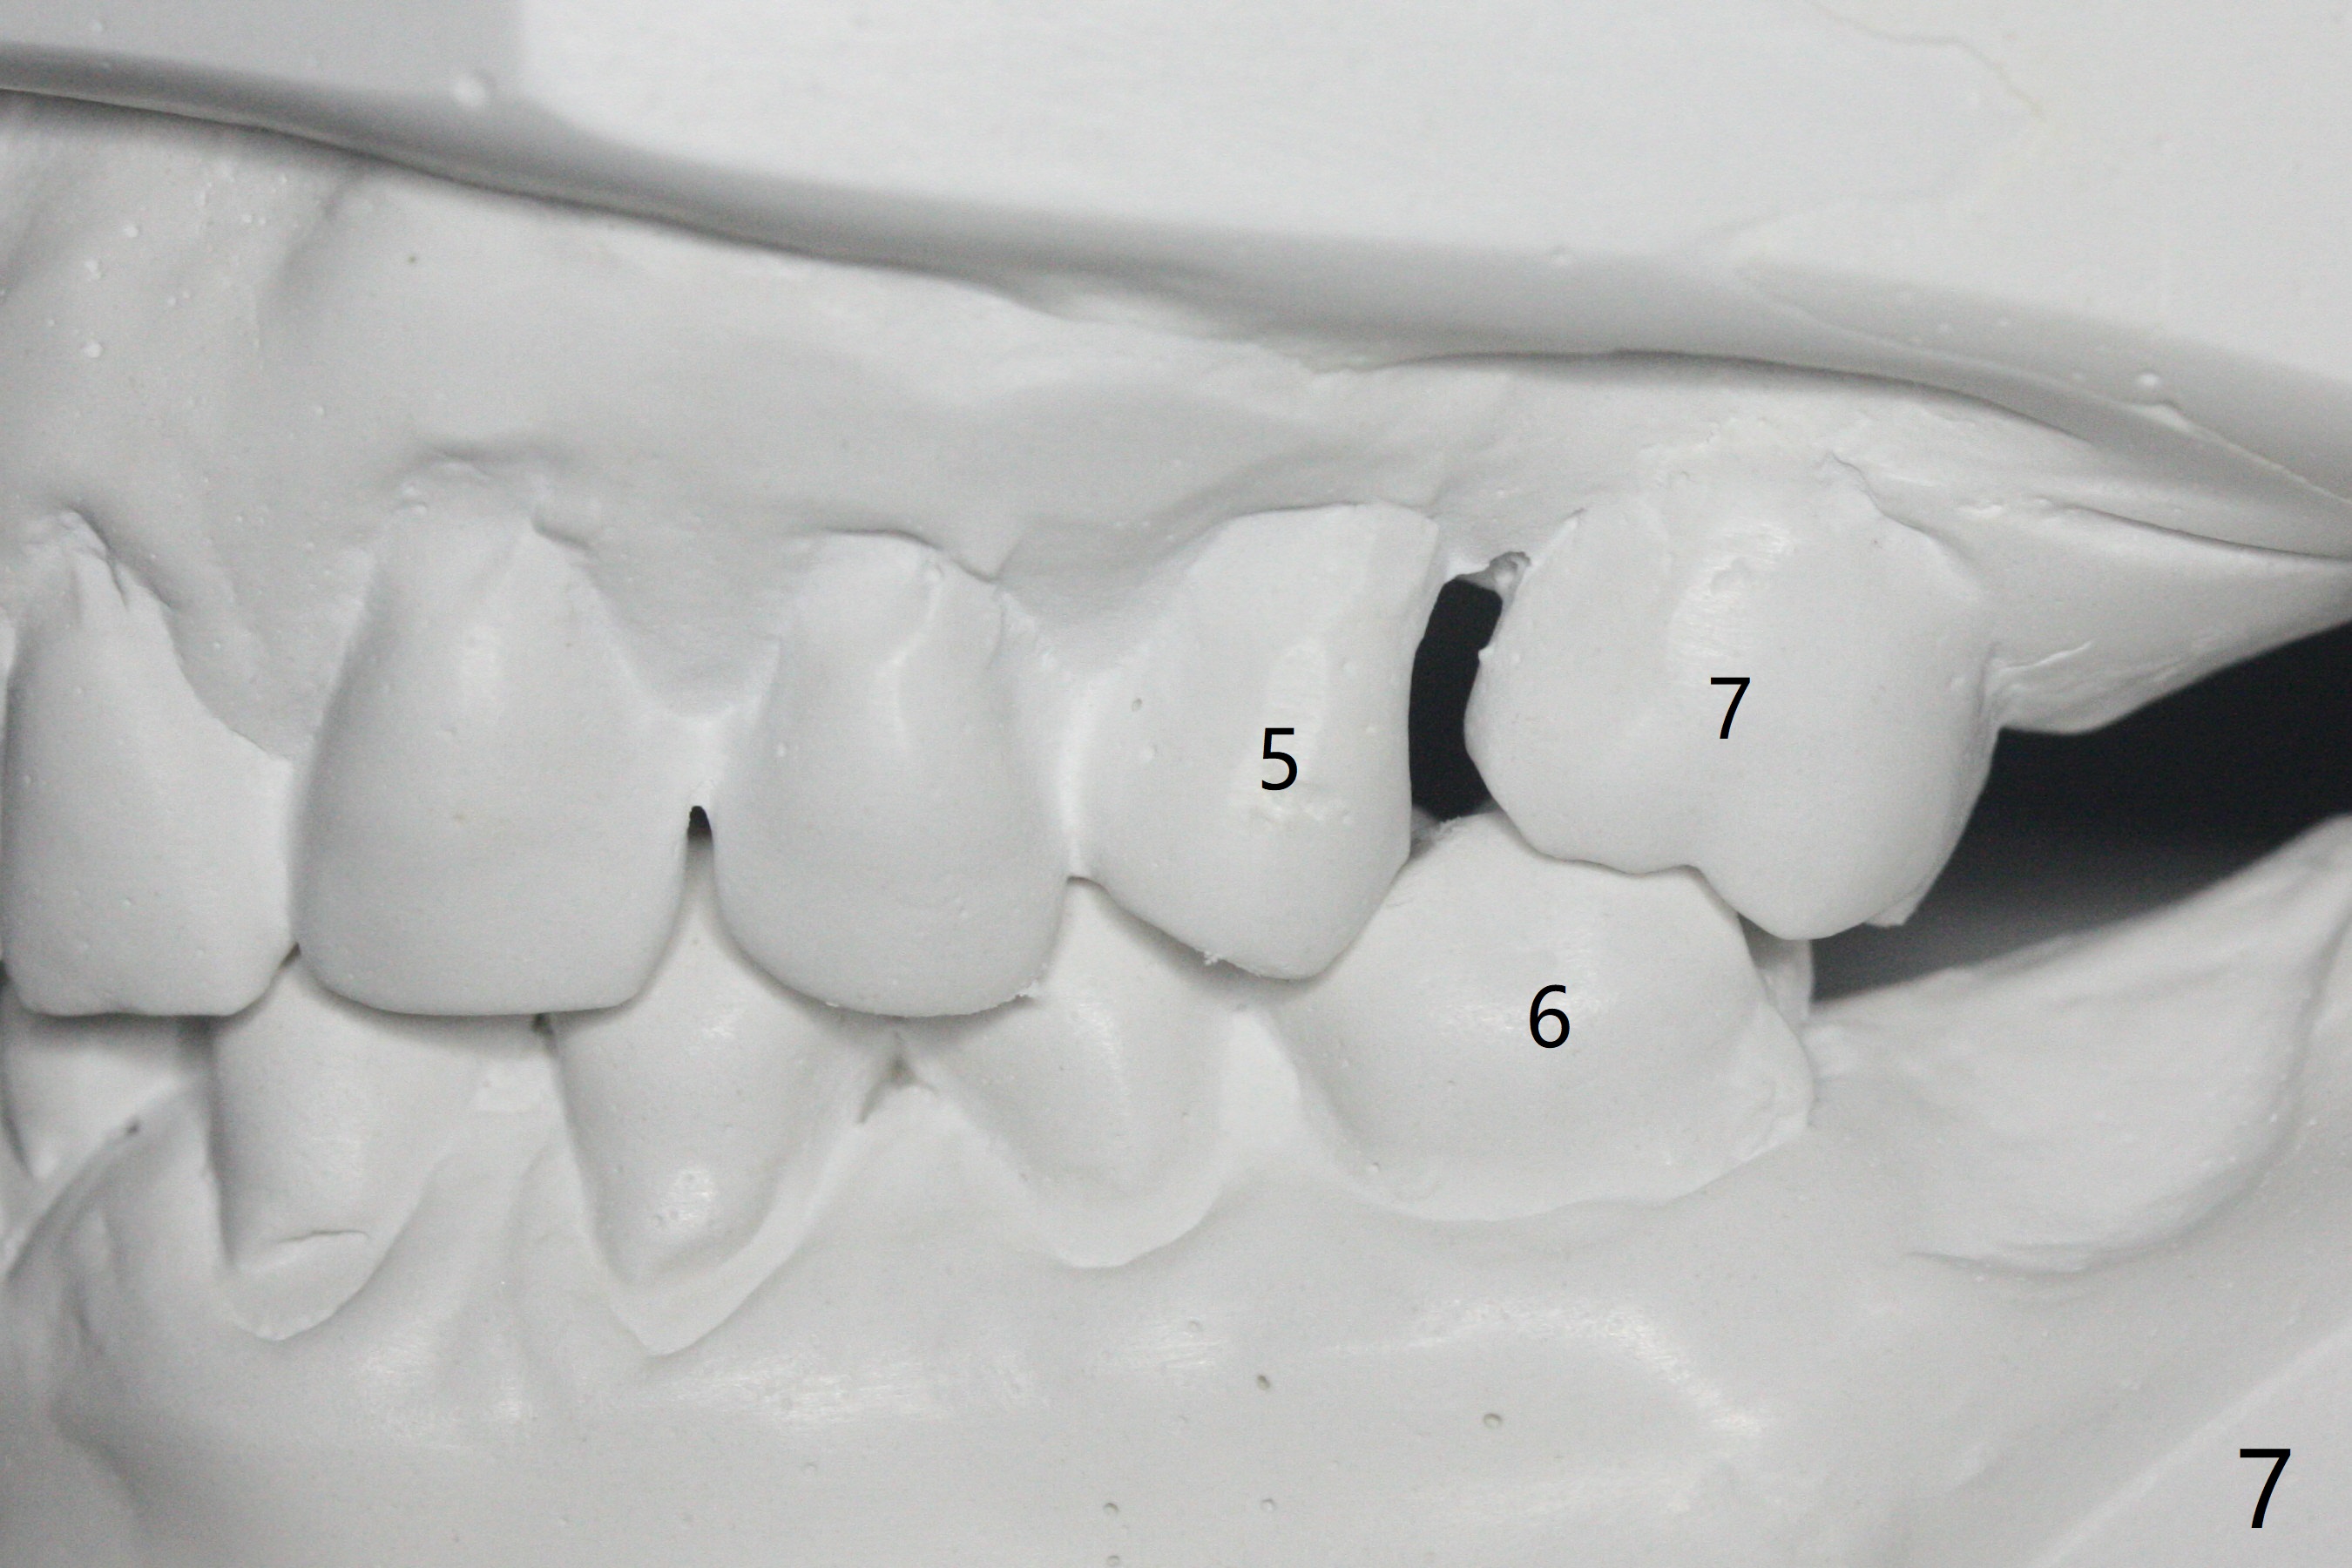

A 54-year-old man returns to office for UL7 upright 6 months post UR5 implant crown cementation (Fig.5,6). The ultimate purpose is to place implants at UL6 and LL 7. The latter will reduce severe occlusal wear especially in the lower anterior teeth (Fig.3,4). To solve the diastema between UR3 and 4 (Fig.1), the bracket at UR3 is placed in the height of contour (Fig.1 insert, Fig.4). Arch wire sequence may automatically close the diastema (Fig.1 insert arrows). In addition to tilting of UL7 (Fig.7), there are diastemata between U1s and UL3 and 4 (Fig.8,9 arrowheads). The patient is not tolerating orthodontic treatment well and requesting finishing the treatment early. We are considering mesializing UL7 instead of upright by placing a mini-implant between UL4 and 5 (Fig.10). There will be less interference of the roots of UL7 with the crown of the impacted UL8. There appears more space for a 1.6x8 mm mini-implant between UL4 and 5 (Fig.11) and UL 3 and 4 (Fig.12). Finally a mini implant is placed distal to UL7.